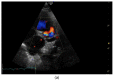

A five-month-old, 3.8 kg intact male Maine coon cat presented for dyspnea characterized by increased respiratory effort in addition to open-mouth breathing. Thoracic radiographs showed pectus excavatum, enlarged cardiac silhouette, and generalized interstitial patterns. Echocardiography revealed normal left atrial (LA) and left ventricular dimensions. A large tubular structure, suspected to be a distended pulmonary vein (PV), was identified as draining into the LA. Severe eccentric and concentric right ventricular hypertrophy and paradoxical septal motion were noted. Based on Doppler echocardiography, both pulmonary venous and pulmonary artery pressure was severely elevated. Clinical, radiographic, and echocardiographic abnormalities were hypothesized to result from pulmonary vein stenosis (PVS), causing severely elevated pulmonary venous pressures and resulting in clinical signs of left-sided congestive heart failure (L-CHF) and severe post-capillary pulmonary hypertension (Pc-PH). The prognosis for good quality of life was assessed as poor, and the owner elected euthanasia. Necropsy confirmed the presence of PVS with severe dilation of the PVs draining all but the left cranial lung lobe. All lung lobes except the left cranial lobe had increased tissue density and a mottled cut surface. This case report shows that, in rare cases, both L-CHF and Pc-PH may be present without LA enlargement. To the authors' knowledge, this is the first report on PVS in veterinary medicine.